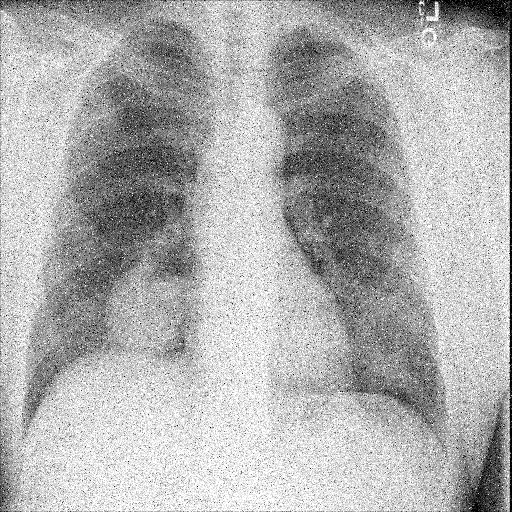

7.2 Qualitative assessment of LDP-processed CXR images

Here, we assume two possible privacy leakage scenarios. To CXR images, we intentionally add features that can lead to the re-identification of the subject appearing in a CXR image. The first feature is an artificial block marker. The second feature is a rare anatomical abnormality known as situs inversus simulated by flipping a CXR image along the vertical axis. Figs. 3(a) and 3(c) show CXR images with the artificial block marker. Fig. 5(a) shows a flipped CXR image to represent a case of situs inversus. We applied DP-GLOW to these CXR images. In Figs. 3(b) and 3(d), the image domain LDP fails to obfuscate the artificial block marker with a moderate privacy budget. In contrast, in Figs. 4(b) and 4(d), DP-GLOW successfully obfuscated the artificial block marker with the moderate privacy budget. On the other hand, the anatomical shape of the chest and the abnormal opacity (hilar regions in the case 1) are preserved. In Fig. 5(b), we observed that the right edge of the heart does not become obfuscated with the image domain LDP. In contrast, in Fig. 6(b), we observed that the right edge of the heart becomes obfuscated and the heart appears at the center of the thoracic cage with DP-GLOW. However, DP-GLOW with this privacy budget is insufficient to almost completely erase the feature of situs inversus.